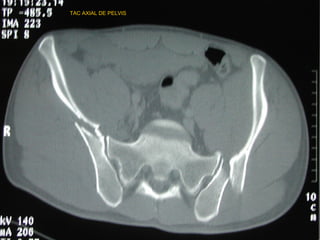

RADIOLOGÍA

• LA IMAGENOLOGIA NO DEBE RETRASAR MANEJO

INICIAL

• TIPO DE IMÁGENES ESTA DADO POR MECANISMO,

GRAVEDAD Y CAPACIDAD DEL CENTRO

• PARTIR DE UNA RX. A.P. PARA DIAGNÓSTICO

• COMPLEMENTARIS : 60°”E”-30°”S” Y OBLICUAS

• TAC : Herramienta de elección en fx. de pelvis

permite evaluar el compromiso óseo, fragmentario,

grados de desplazamiento, compromisos

abdominopélvicos y diferenciar hematomas retro e

intra abdominales

• Uretrocistograma en caso de hematuria franca

• Angiografía :evidencia de hematom retroperitoneal

y perdida de mas de 4 unidades de GR

TAC AXIAL DE PELVIS

TAC HELICOIDAL FRONTAL

TAC HELICOIDAL AXIAL